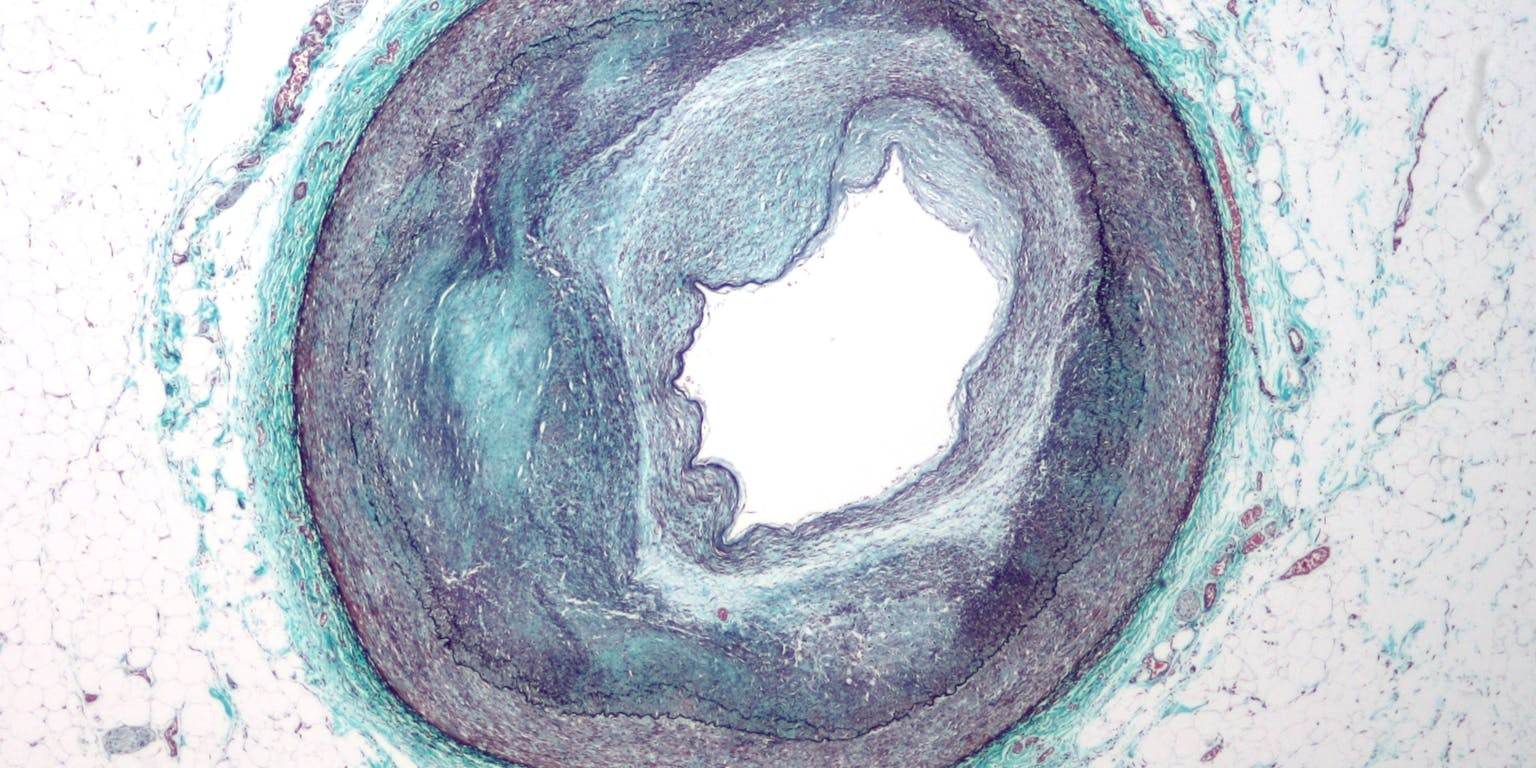

Aangekleurde opname van een doorsnede van een slagader die voor nog slechts 25 procent geopend is. Het grillig gevormde middenstuk is de groeiende plaque.

Wikimedia Commons“De moeilijkheid blijft dat in een vergevorderd stadium van atherosclerose de plaque een heel complex en ondoordringbaar geheel is geworden. Het begint heel eenvoudig als een klompje macrofagen vol vetbolletjes, maar gaandeweg ontstaat daar een beschermend bindweefselkapje omheen waardoor de plaque alleen nog maar moeilijker afbreekbaar en bereikbaar wordt. Er is dus nog veel onderzoek nodig.”